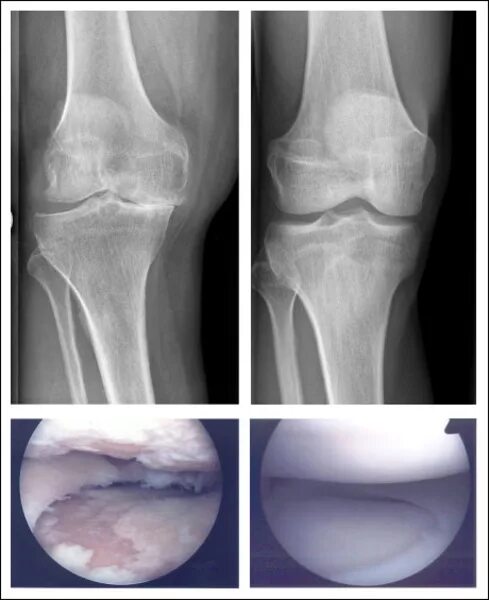

Повреждение хряща по outerbridge